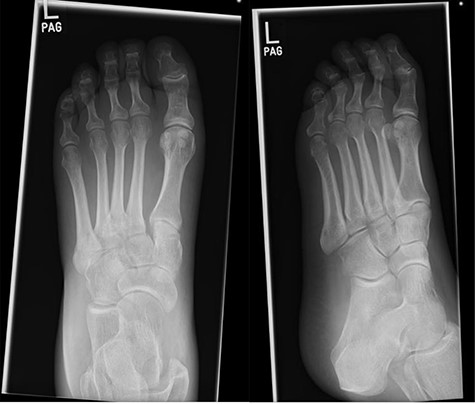

Initial foot X-rays (AP and lateral views), exhibiting normal appearances.

A 41-year-old female, with a background of Type 1 Diabetes Mellitus (T1DM), previous diabetic foot infection and peripheral neuropathy, presented acutely with a hot, swollen and erythematous left foot. Ten days prior, she sustained a fall whilst walking. The patient denied injury, swelling or pain at the time, though she presented to the emergency department (ED) 2 days following the fall with a new-onset foot swelling. Initial imaging with plain film X-ray, as well as blood tests, was unremarkable (Fig. 1), and she was discharged from the ED. A plantar blister appeared over the following days, with subsequent worsening of foot swelling and erythema over a 10-day period, culminating in her acute presentation (Fig. 2).